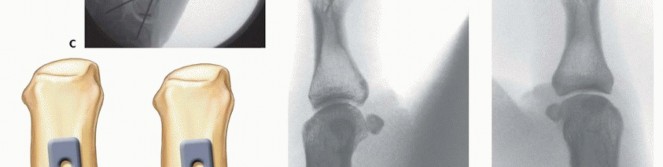

Fixation Strategies for Rolando and Comminuted Patterns

Rolando fractures present a significantly higher degree of complexity. The classical Y or T pattern often precludes simple lag screw fixation. In these instances, mini-fragment plating is the gold standard. T-plates or specialized condylar plates are contoured to fit the complex geometry of the metacarpal base. The articular fragments are first reduced and provisionally pinned, essentially converting the complex intra-articular fracture into a simpler two-part extra-articular fracture. The plate is then applied to buttress the articular fragments and bridge the metaphyseal comminution to the diaphysis.

Image